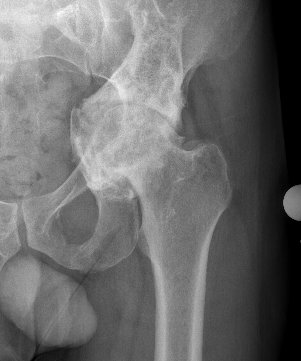

Abnormal protrusion of the femoral head into the acetabulum

- centre edge angle > 40o

- protrusion of the acetabulum beyond ilioischial line / Kohlers line

Sotelo-Garza / Charnley classification

Medial wall of acetabulum as ilioischial line

Grade I: Mild protrusion 1-5mm

Grade II: Moderate protrusion 6-15 mm

Grade III: Severe protrusion >15 mm